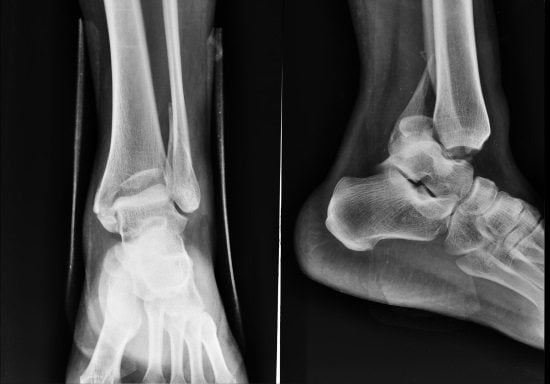

Перелом – это достаточно распространенный вид травмы голеностопного сустава, на долю которого приходится около 15% от общего числа механических повреждений костно-суставных сегментов опорно-двигательного аппарата. Происходит опосредованное воздействие травмирующей силы, то есть при жестком фиксировании задней части стопы ее передний отдел продолжает движение. Травма (перелом) голеностопа возможна при падении с высоты, в результате неудачного приземления при выполнении физических упражнений, катании на лыжах, коньках. При получении травмы дальнейшее перемещение или движение человека становится весьма ограничено, так как голеностопный сустав болит. Что делать?

Не следует производить пораженной нижней конечностью какие-либо физические действия. Человеку нужна помощь медицинского работника и абсолютный покой, так как характер повреждения можно определить лишь при рентгенологическом исследовании. Нужно немедленно доставить пациента в ближайшее медицинское учреждение или вызвать Скорую помощь.